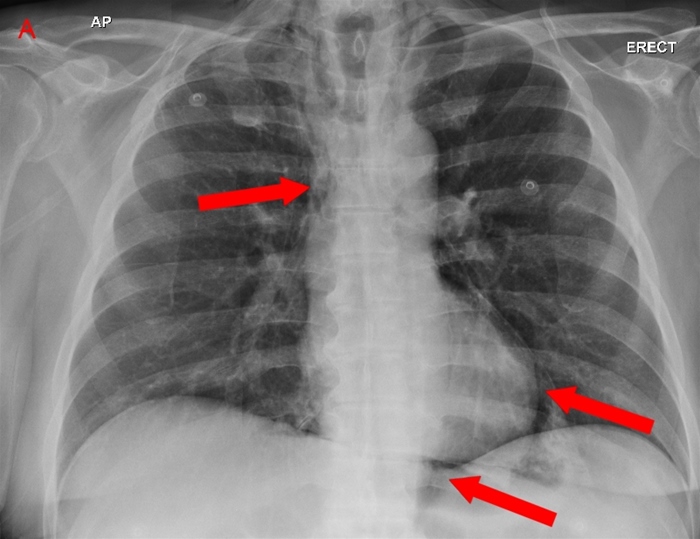

Pulmonary Contusion

Pulmonary contusions are parenchymal injuries that can cause hypoxia in the acute setting. Classically, pulmonary contusions may not be immediately apparent radiographically, but later show a bilateral "white-out" appearance due to diffuse opacities.

Pulmonary contusions have a similar pathophysiology to ARDS in that they are characterized by increased vascular permeability and intraalveolar hemorrhage. Besides breathing and oxygenation monitoring, treatment of pulmonary contusion centers around fluid restriction and diuretics.

Acute respiratory distress syndrome (ARDS) is a common complication of PC. However, ARDS usually manifests 24-48 hours after trauma and demonstrates bilateral, patchy alveolar infiltrates on chest x-ray.